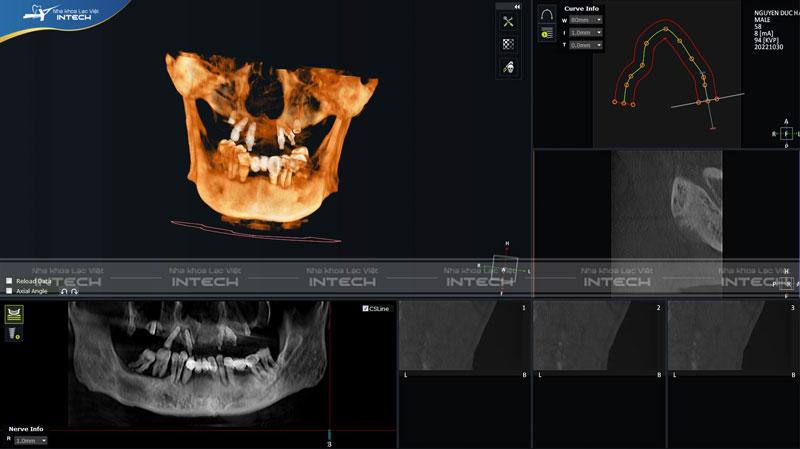

Qua khảo sát phim CT Conebeam cũng như tiến hành thăm khám cho chú Hà, bác sĩ Nguyễn Hoàng Dương - Chuyên gia cấy ghép Implant tại Nha khoa Lạc Việt Intech đã đưa ra kế hoạch điều trị cho chú Hà:

Dưới đây là hình ảnh phim X-quang của chú Hà sau khi tiến hành cấy ghép răng Implant All On 6 hàm trên bằng công nghệ Safe Tech.

Hình ảnh phim chụp CT của chú Hà sau khi cấy ghép 6 trụ Implant hàm trênHình ảnh phim chụp CT của chú Hà sau khi cấy ghép 6 trụ Implant hàm trên

Khảo sát qua phim CT, có thể thấy sau khi tiến hành phẫu thuật tăng thể tích xương và nâng xoang thì vị trí xương hàm bên phải đã tăng lên 8,89mm còn ở bên trái thì xương đã tăng đến 10mm. Các trụ Implant được phân bố đều, giúp nâng đỡ toàn bộ hàm giả và ngay sau khi cấy ghép Implant bác sĩ đã hẹn lịch lắp răng sau khoảng 2 ngày. Nhờ đó bệnh nhân có thể ăn nhai dễ dàng và thẩm mỹ tốt hơn.

Với sự hỗ trợ của công nghệ Safe Tech, bác sĩ có thể dễ dàng đặt trụ Implant đúng vị trí một cách chính xác. Khi trụ Implant được đặt chính xác trong xương hàm, khả năng chịu lực cũng như tích hợp xương của trụ Implant sẽ đạt đến tối đa.